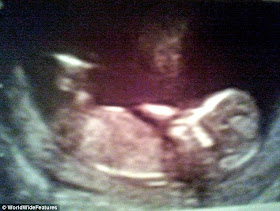

Η υπερβολική σιγουριά τους οφειλόταν στην εικόνα που βλέπετε! Ήταν έγκυος μόλις 12 εβδομάδων, όταν η 31χρονη, έκανε υπερηχογράφημα και αντίκρυσε κάτι παράξενο. Παρατήρησαν καλύτερα και είδαν τη μορφή ενός προσώπου πάνω από το σώμα του εμβρύου! Θεώρησαν πως ήταν ο φύλακας άγγελος του μωρού τους και έκρυψαν τον υπέρηχο για να τον δείξουν στο γιό τους όταν θα γεννιόταν.

Έξι μήνες μετά, όταν τελικά η Ντι αναγκάστηκε να γεννήσει το μωρό στο σπίτι, μακρυά από νοσοκόμες και γιατρούς, βεβαιώθηκαν πως πράγματι κάποιος φρόντισε ώστε όλα να πάνε καλά!

" Όταν γέννησα τον γιο μου στο πάτωμα του μπάνιου, δεν υπήρχε κάποια μαία να με βοηθήσει, παρά μόνο η μητέρα μου. Κι όμως είχα σιγουριά και ασφάλεια γιατί βλέποντας αυτήν την εικόνα ήξερα ότι υπήρχε κάποιος που πρόσεχε το μωρό μας", δήλωσε η μητέρα στη Daily Mail!